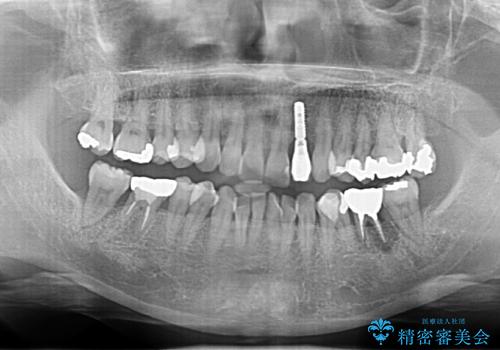

- 左下奥歯の歯ぐきの違和感で来院。

昔神経の治療をした歯が割れてしまっていました。

やむなく抜歯になりましたが、その部分にインプラントを始め希望されましたが、炎症により、骨がなく、かつ歯並びの関係で入れても歯ブラシができずにインプラントも長くもたなそうという診断になりました。

インプラントではなくブリッジにするためには、奥歯の並びを矯正しておいた方がいい状態でした。

抜歯後に部分的にワイヤー矯正を半年ほど行ってから、ブリッジを入れる治療を行いました。

奥歯の部分矯正を行うことで、歯の傾きが良くなり、結果神経を取らずにブリッジを入れていくことができました。

通常矯正治療後は歯並びが戻らないように保定が必要ですが、ブリッジを入れているので歯並びは戻らないため保定が不要です。

部分矯正と補綴の相性は良いといえます。